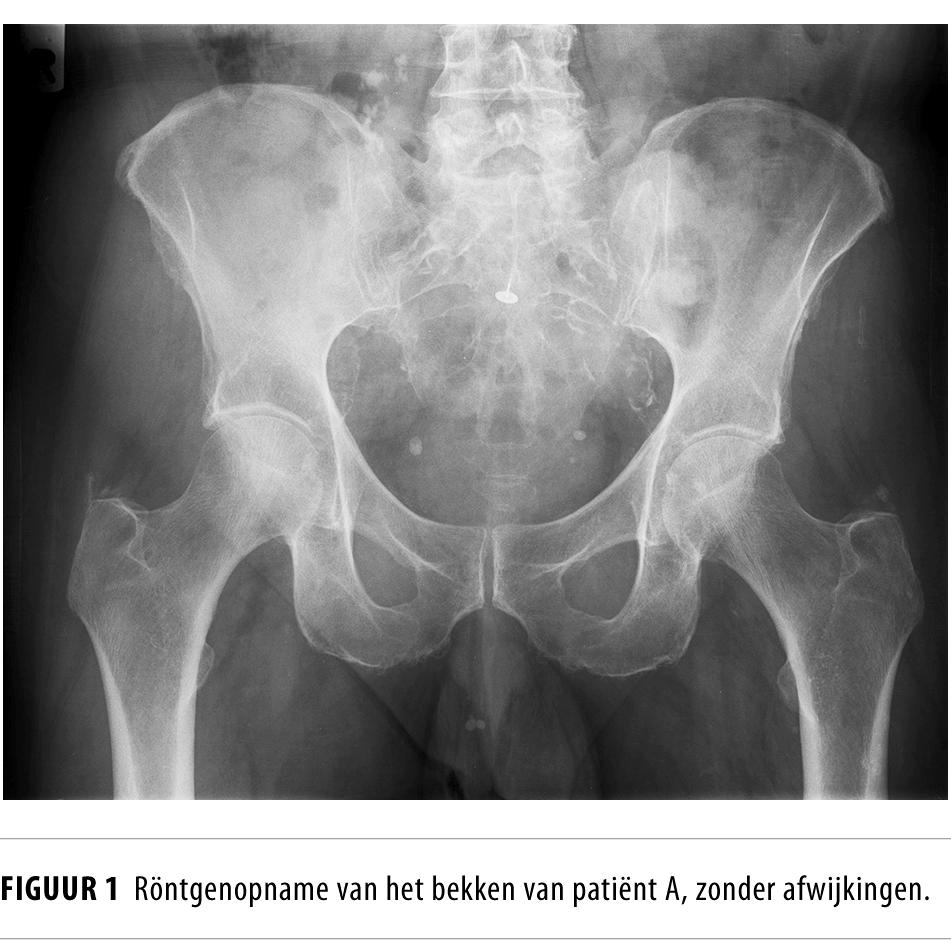

Liespijn bij sporters NTvG